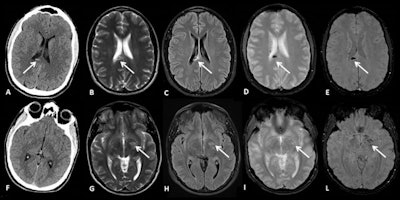

A 25-year-old male sustained direct head trauma due to a high-speed fall (forward, over the handlebars) after hitting an obstacle on the trail. He appeared sleepy and inattentive at the neurologic examination. Axial CT scan (A, F) shows a small hemorrhagic lesion in the splenium of the corpus callosum (arrow in A). A subsequent MRI scan obtained two days later confirmed the finding and showed other punctate lesions in the left basal ganglia that appear hyperintense on T2-weighted (B, G) and FLAIR sequences (C, H), and hypointense on gradient echo (D, I) and susceptibility-weighted sequences (E, L), suggestive of diffuse axonal injury lesions. All images courtesy of Dr. Raffaella Colantonio and colleagues and presented at ECR 2023.

A 25-year-old male sustained direct head trauma due to a high-speed fall (forward, over the handlebars) after hitting an obstacle on the trail. He appeared sleepy and inattentive at the neurologic examination. Axial CT scan (A, F) shows a small hemorrhagic lesion in the splenium of the corpus callosum (arrow in A). A subsequent MRI scan obtained two days later confirmed the finding and showed other punctate lesions in the left basal ganglia that appear hyperintense on T2-weighted (B, G) and FLAIR sequences (C, H), and hypointense on gradient echo (D, I) and susceptibility-weighted sequences (E, L), suggestive of diffuse axonal injury lesions. All images courtesy of Dr. Raffaella Colantonio and colleagues and presented at ECR 2023."Mountain biking accidents can lead to a wide variety of injuries involving the head and face, neck, spine and spinal cord, upper and lower extremities, chest, abdomen, and genitourinary system," they wrote, adding that Santa Chiara's has become the treatment hub for trauma patients in the autonomous province of Trentino.